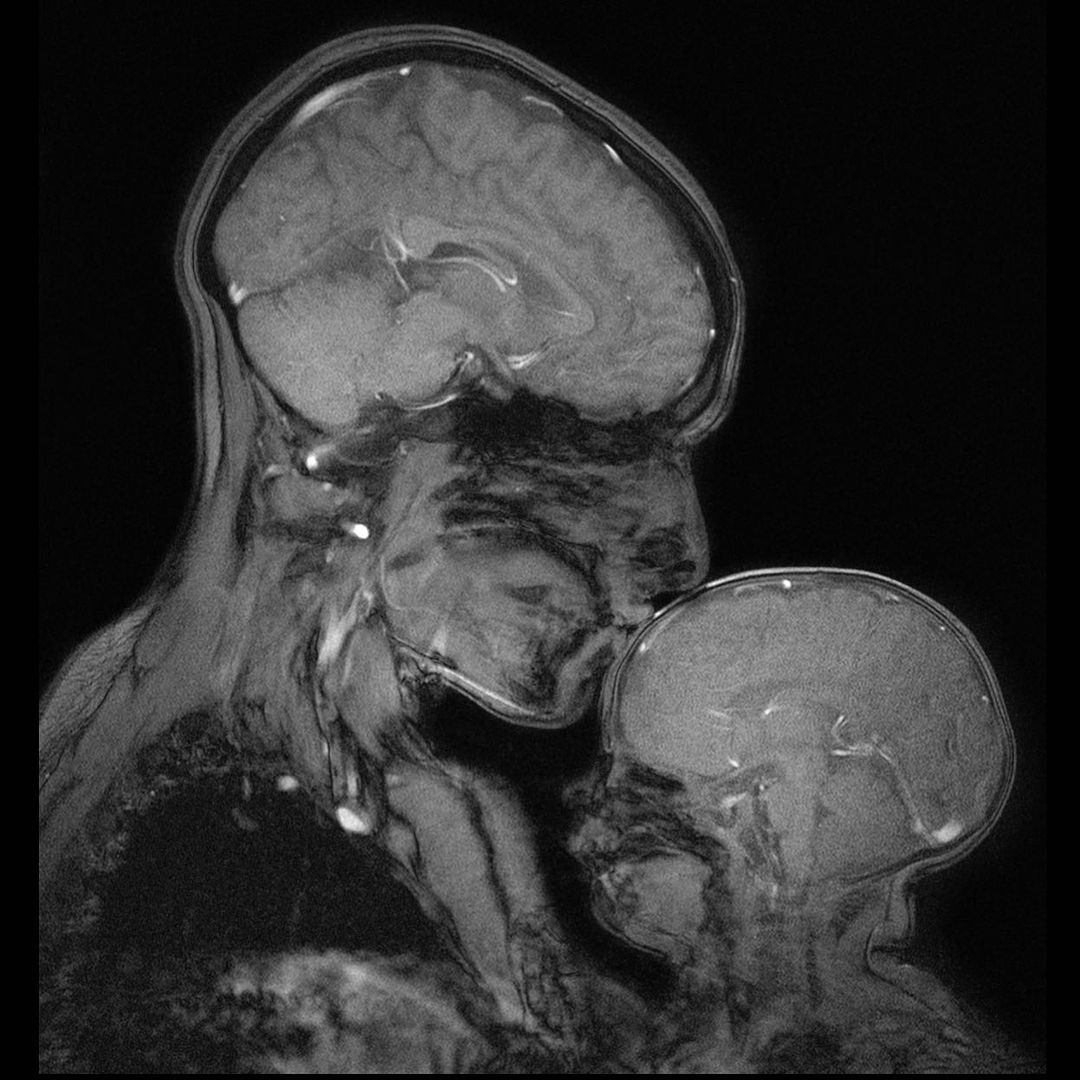

Rebecca Saxe and Atsushi Takahashi captured this stunning MR image of a mother and child. Link in bio to learn about the motivation and people behind this iconic image.